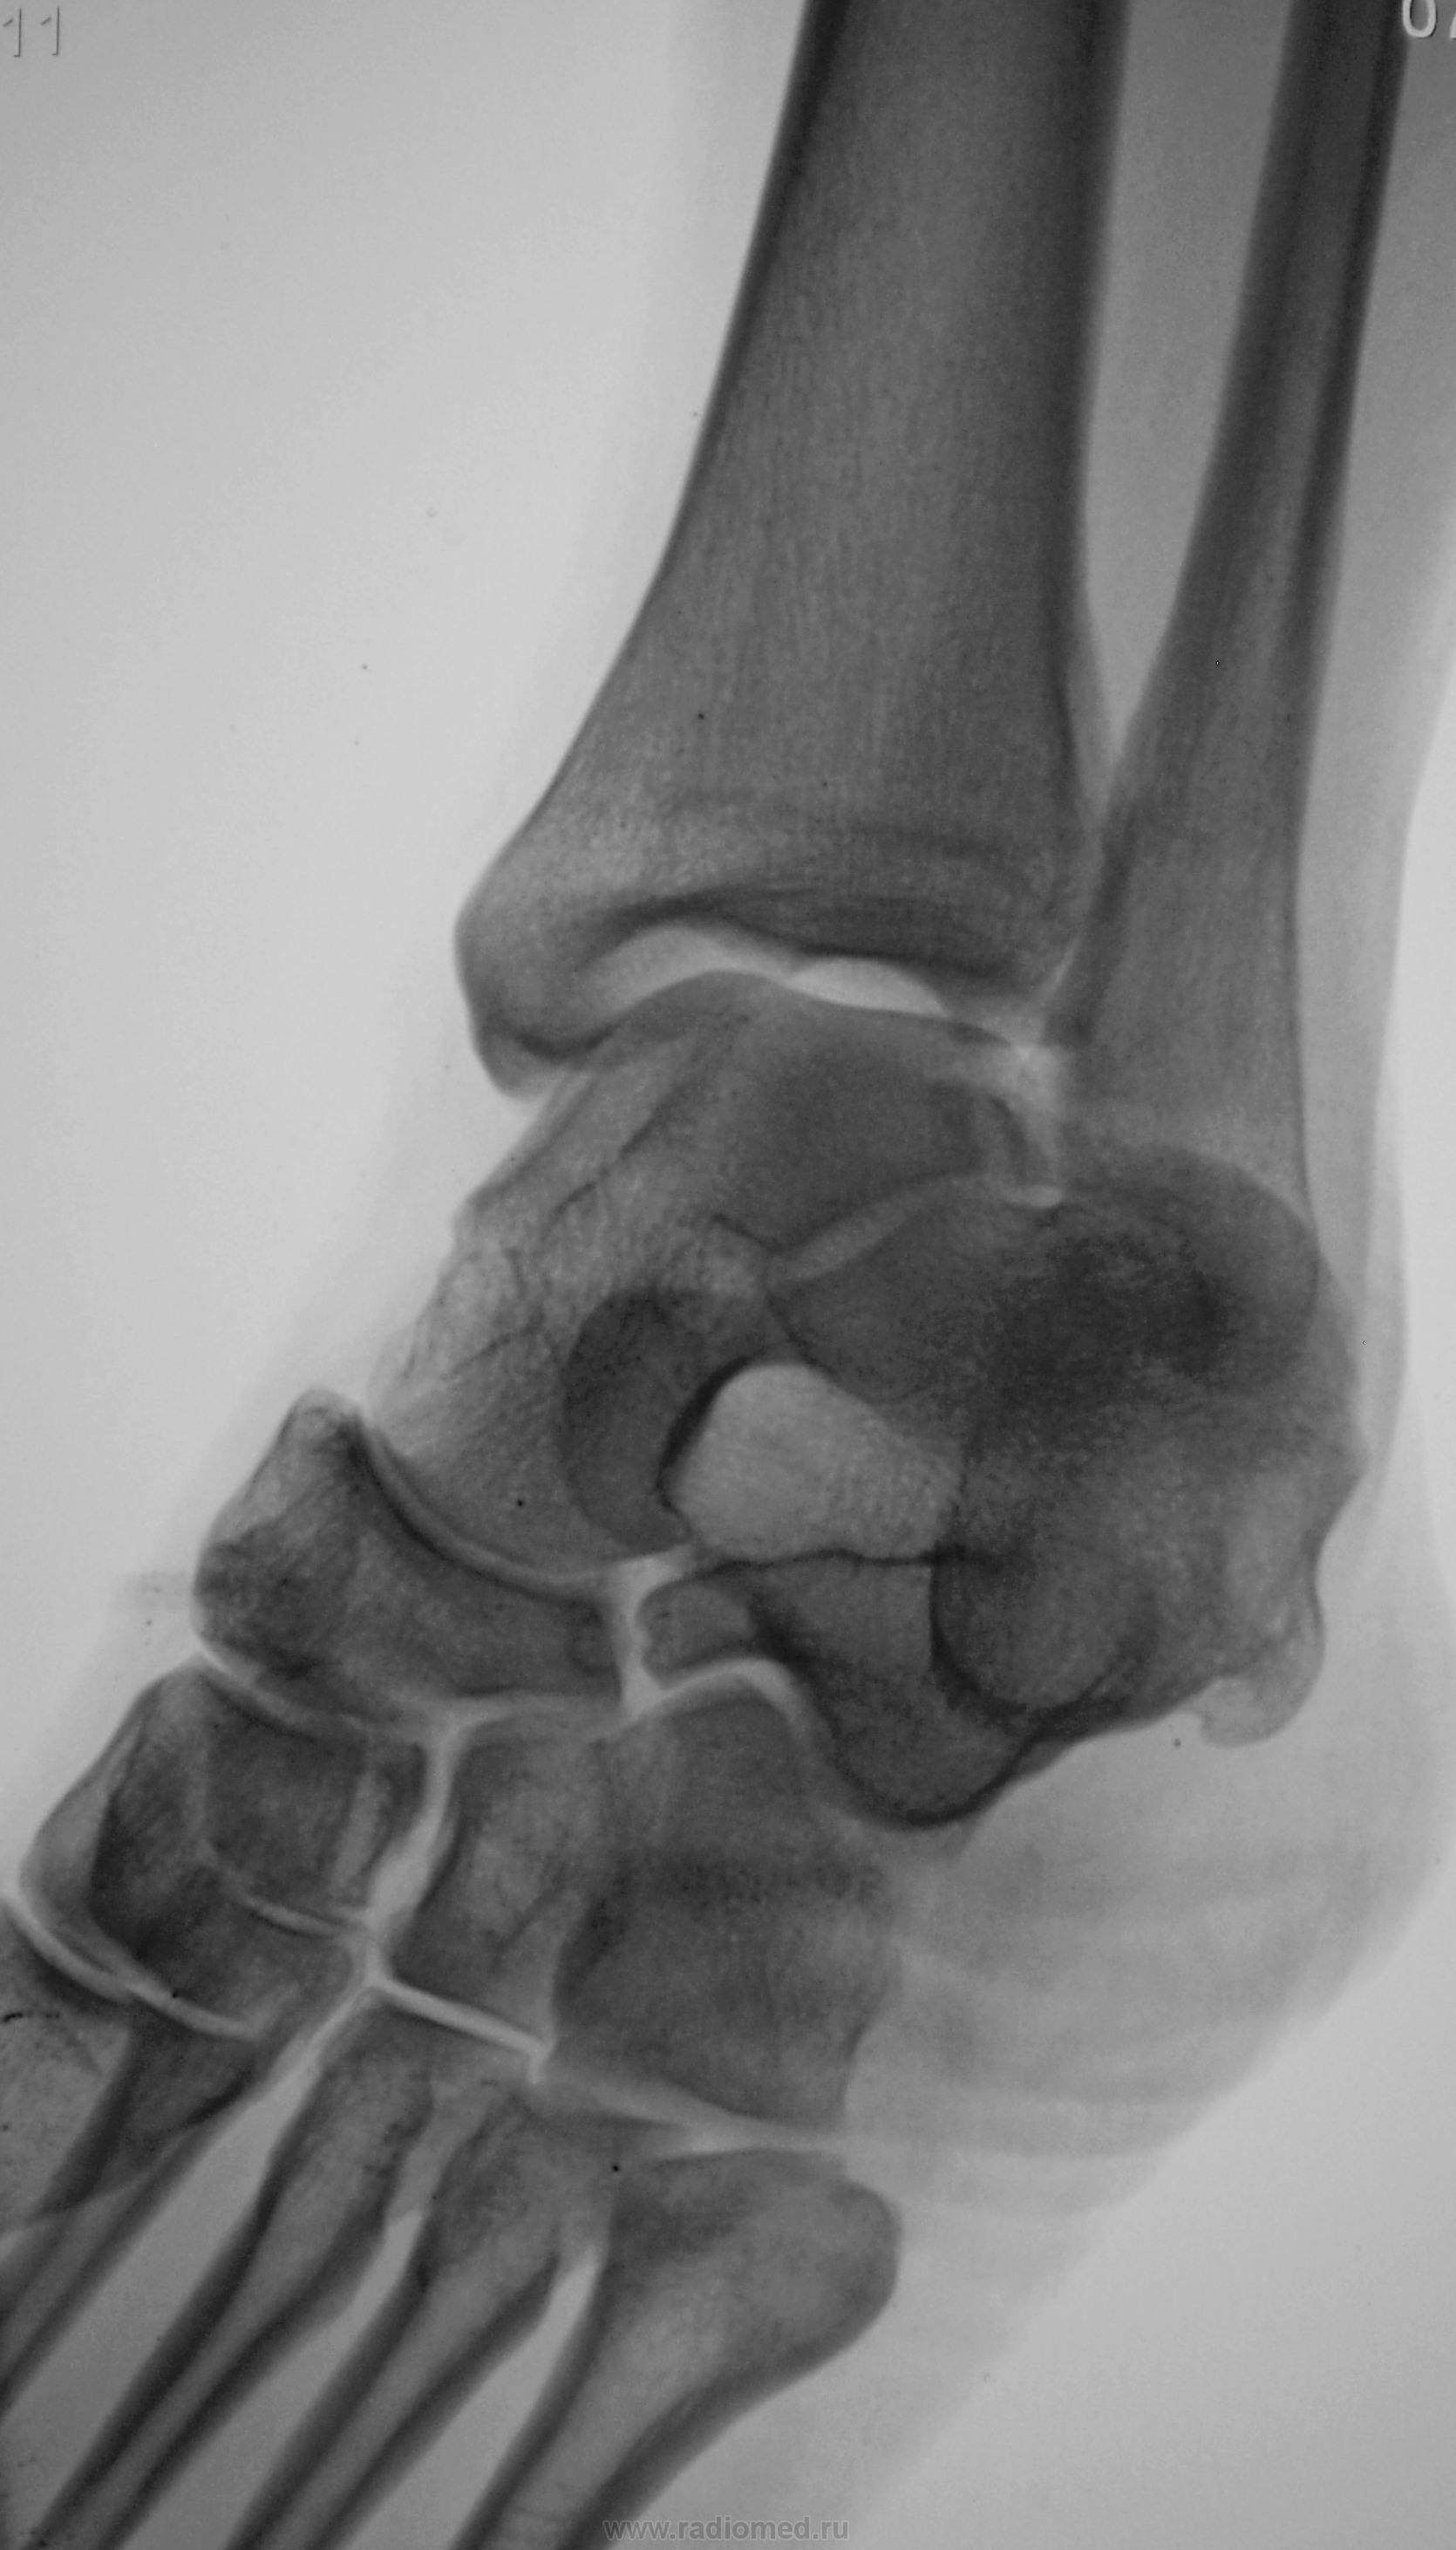

Травма.  Пациент направлен на рентгенографию голеностопного сустава.